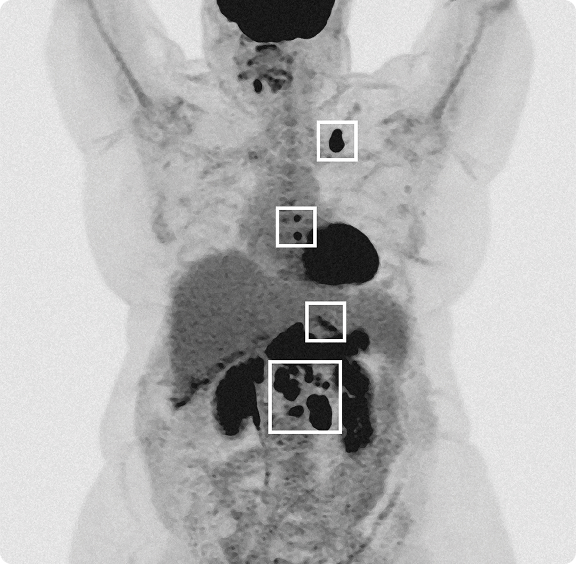

Wenn der Krebs nicht im Ursprungsorgan bleibt, sondern sich im Körper weiterverbreitet – zum Beispiel in Lymphknoten, Leber oder Knochen, spricht man von Metastasen (Ablegern). Die Verbreitung der Krebszellen erfolgt meist über die Blut- oder Lymphbahn. Am neuen Ort wächst die Metastase dann wie der Primärtumor und verdrängt wiederum gesundes Gewebe.

Um die Wirksamkeit der Therapien und die Entwicklung der Metastasen beurteilen zu können, erfolgen engmaschige radiologische oder laborchemische Kontrollen.